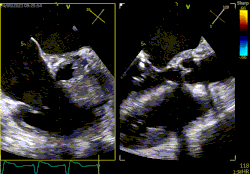

A betegreferálásra jelenleg heti két alkalommal van lehetőség, hétfőn és csütörtökön. A megbeszélések során a beteg anamnézisét és aktuális klinikai állapotát figyelembe véve, a rendelkezésre álló képalkotó vizsgálatok áttekintését követően születik multidiszciplináris döntés.

1. Szívbillentyű-betegségek esetén az intervenciós vagy sebészi megoldásra való alkalmasság elbírálása

5. ASD és PFO intervenciós vagy sebészi megoldásának megítélése